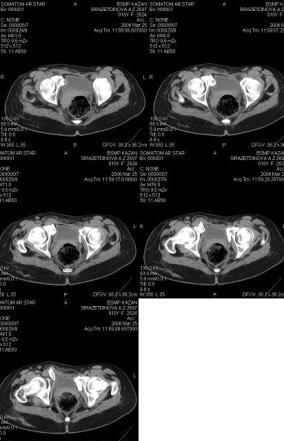

Предоставляю срезы. Если пациентку функционально ничего не беспокоит, стоит ли навязывать ей лечение.

Для уточнения диагноза ниеобходимы обзорные рентгенограммы таза (прямая и inlet), Кт срезы на уровне переломов для определения степени сращения и решения вопроса о методе оперативного восстановления анатомии (делать ли остеотомию, низводить ли задние отделы), ни о какой "остеотомии выступающих отломков" тем более у девочки 18 лет речи быть не может.